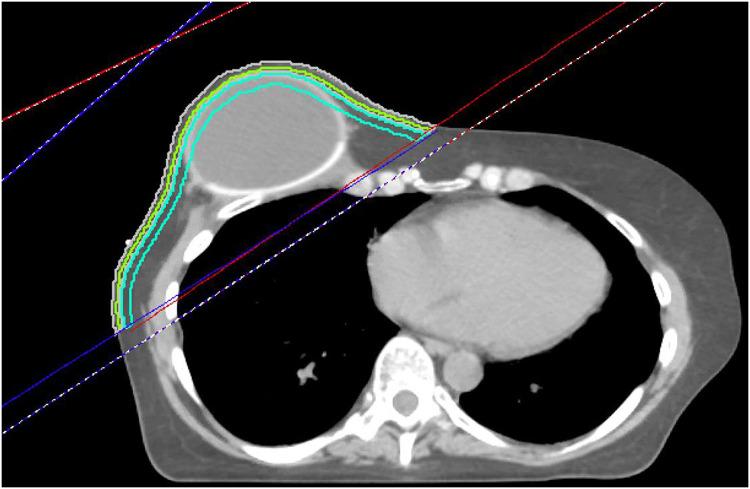

Patients receiving PMRT at a single institution from 2016 to 2019 were retrospectively reviewed. Patient demographics and treatment information were collected. Three near-surface structures were retrospectively generated, bound by the chest wall tangent beam as well as the skin surface and the skin-3 mm contour (SR3), skin surface and skin-5 mm contour (SR5), or skin-5 and skin-10 mm contours. Dosimetric analysis of these near-surface contours was performed in 2 Gy intervals. Univariate and multivariate analyses were used to identify predictors of moist desquamation, grade 2+ chest wall pain, use of opiate pain medication, unplanned reconstructive surgery, and implant failure. Logistic regression for each outcome and near-surface contour was performed for receiver-operator area under the curve (AUC) analysis and the Youden J Statistic was used to determine the optimal threshold for each dosimetric parameter.